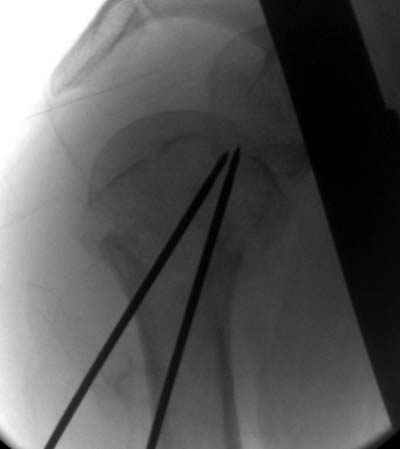

Сегодня взял больного повторно в операционную, не скажу, что повторная репозиция через неделю после первой попытки, была простая.

После удаления спиц попытался манипулировать отломками, но безуспешно, поэтому пришлось пользоваться периостальным элеватором, чтобы устранить смещение отломков и перепровести спицы. Проверил и перепроверил стабильность фиксации под ЭОПом, завтра Рг- будет готов, вот и поглядим....